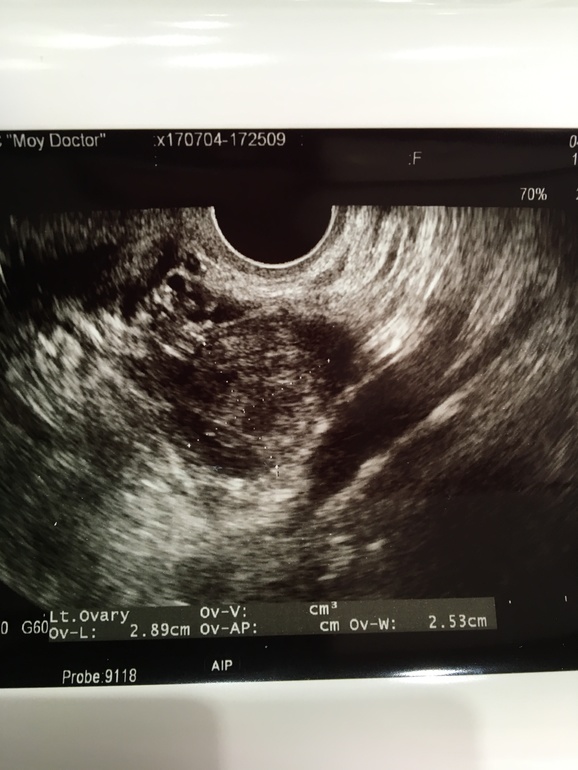

У меня такая же ситуация, О была на 19 ДЦ, а на 23 ДЦ на узи поставили диагноз киста ЖТ. Пью дюфастон 200 мг в день, сегодня 25 дц, пошла к другому узисту, тоже ставит кисту, но кровоток вокруг нее есть, хоть и слабый. Вот и думаю, ждать ли //)) Вам кисту на какой день цикла нашли?

А вот на УЗИ мне всё равно ничего не понятно ) я только словесные УЗИ понимаю 😂